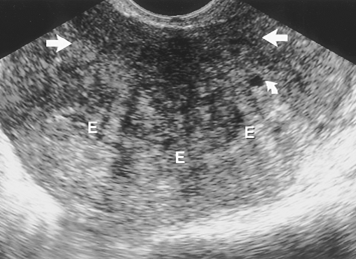

Siêu âm đầu dò âm đạo: thường gặp nhất là vùng giảm âm hay không đồng nhất của lớp cơ không rõ ranh giới, không gây hiệu ứng khối, có thể thấy những ổ dịch nhỏ (50% BN) do giãn nang tuyến hay chẩy máu thường < 5mm. sự dầy lên của lớp cơ tạo hình ảnh lệch tâm của buồng nội mạc,

![]() |

| Lạc nội mạc tử cung làm cơ tử cung mất cân đối qua đường niêm mạc |